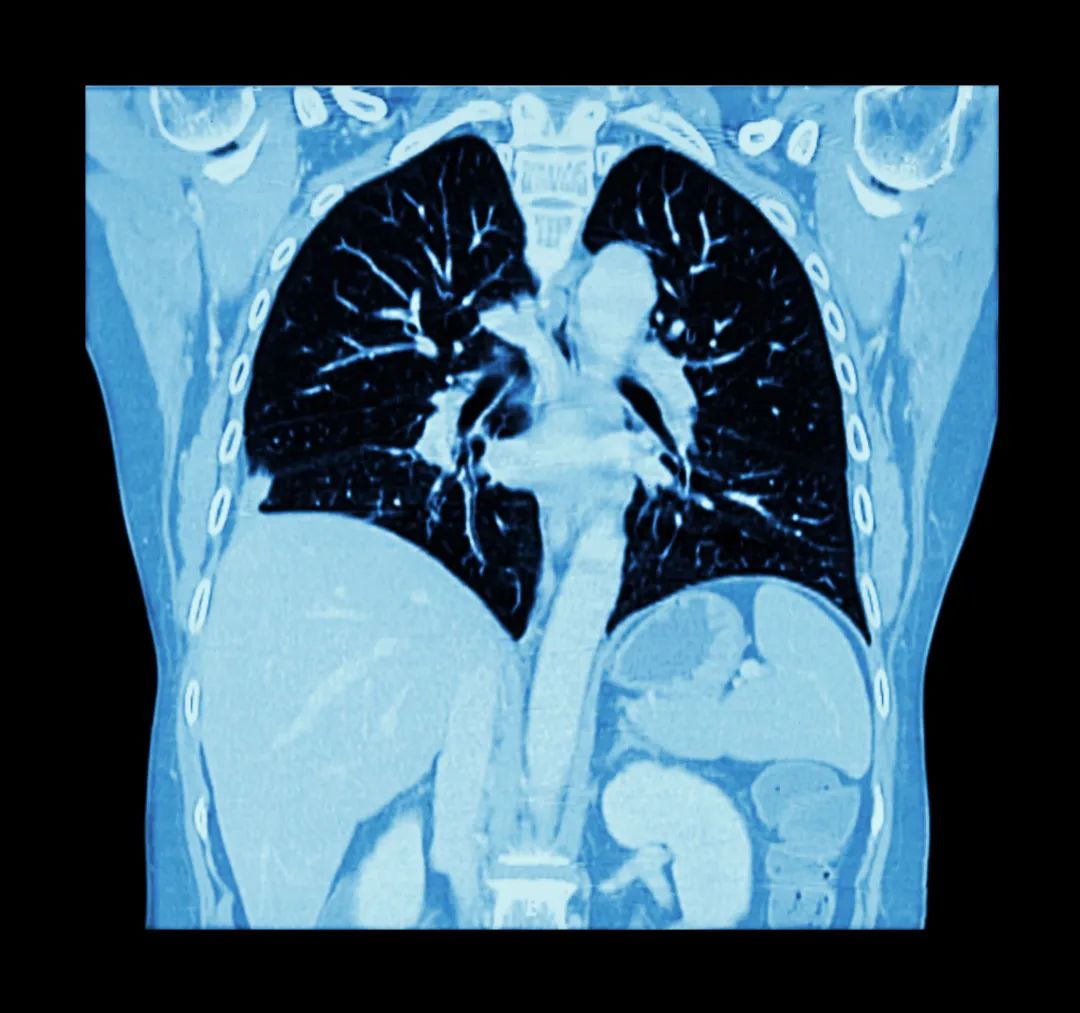

面对肿瘤中高发的肺癌,您了解肺癌的早期症状和筛查方法吗?每年11月是全球肺癌关注月,关于肺癌的9个高危症状要当心!

一般来说,初次CT检查发现的肺部结节80%-90%都是良性病变。但如果身上出现以下两种肺结节,最好要足够重视,定期随诊,必要时手术切除。

1. 看结节的大小和形态,如果结节大小8毫米以上,结节边界不清的,分叶状,边缘毛刺,结节内有空泡及血管穿行等特点,需要定期复查。复查中结节有增大或实性成分增多,最好通过相关诊治手段协助明确或者手术切除,这类结节随着时间的推移,有可能变成肺癌。

肺癌的存活率与发现时的分期有很大关系。但早期肺癌很多没有明显的症状,因此很难被及早发现。及时筛查是发现肺癌的关键。对于肺癌高危人群,建议行低剂量螺旋CT筛查。